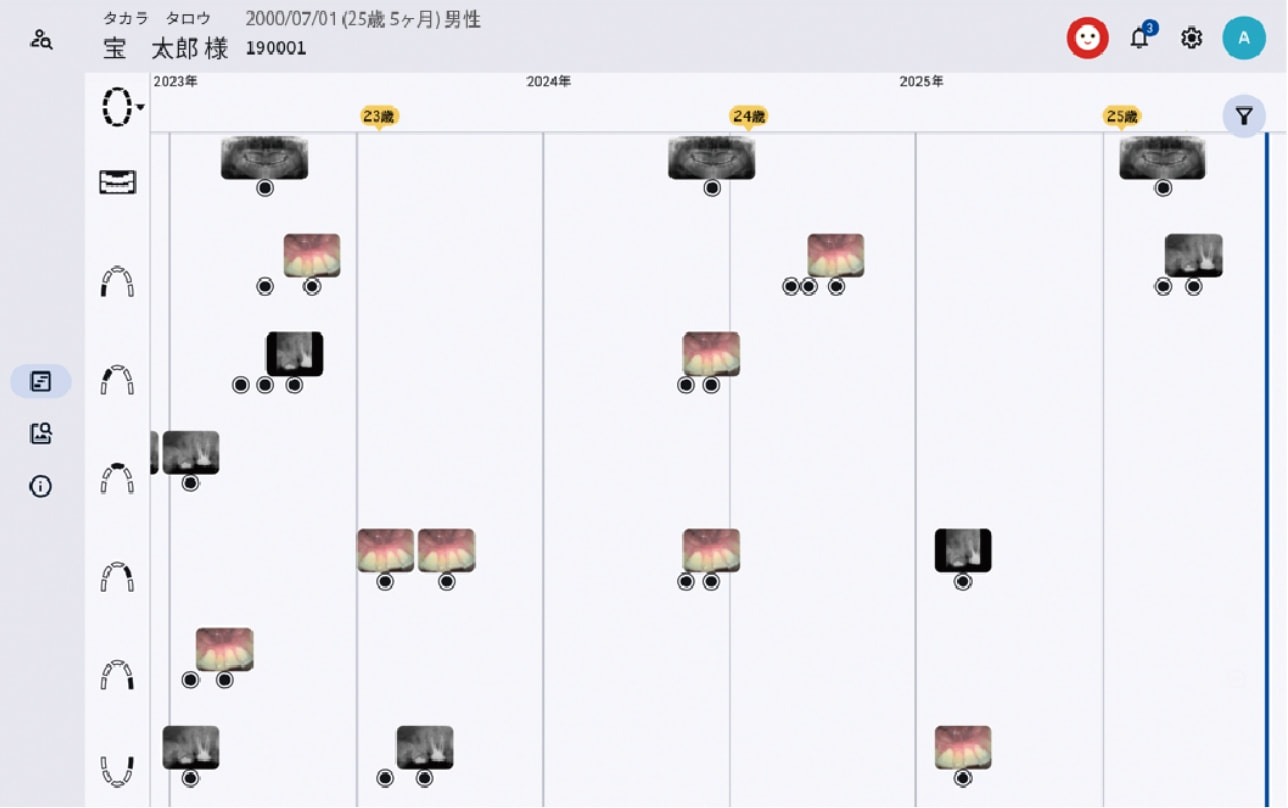

タイムライン表示

過去から現在までの口腔内データを時系列で追跡し、変化の積み重ねを“見える化”することで、診断はもちろん、予防・メンテナンスの説明も支援します

ライフタイムチャート表示

患者さんの一生涯に渡るレントゲンや口腔写真等を、部位ごとに時系列に沿って一覧で配置。

撮影の間隔や頻度を、直感的に把握できます